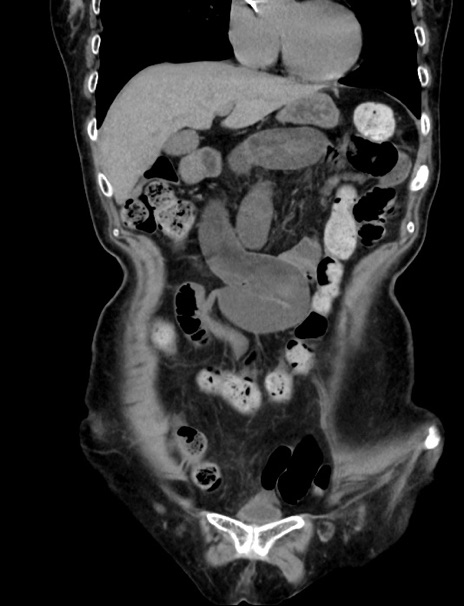

横断像